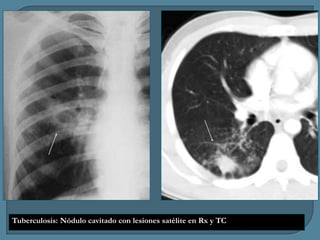

Tuberculosis: Nódulo cavitado con lesiones satélite en Rx y TC

Tuberculosis: Nódulo cavitadocon lesiones satélite en Rx y TC